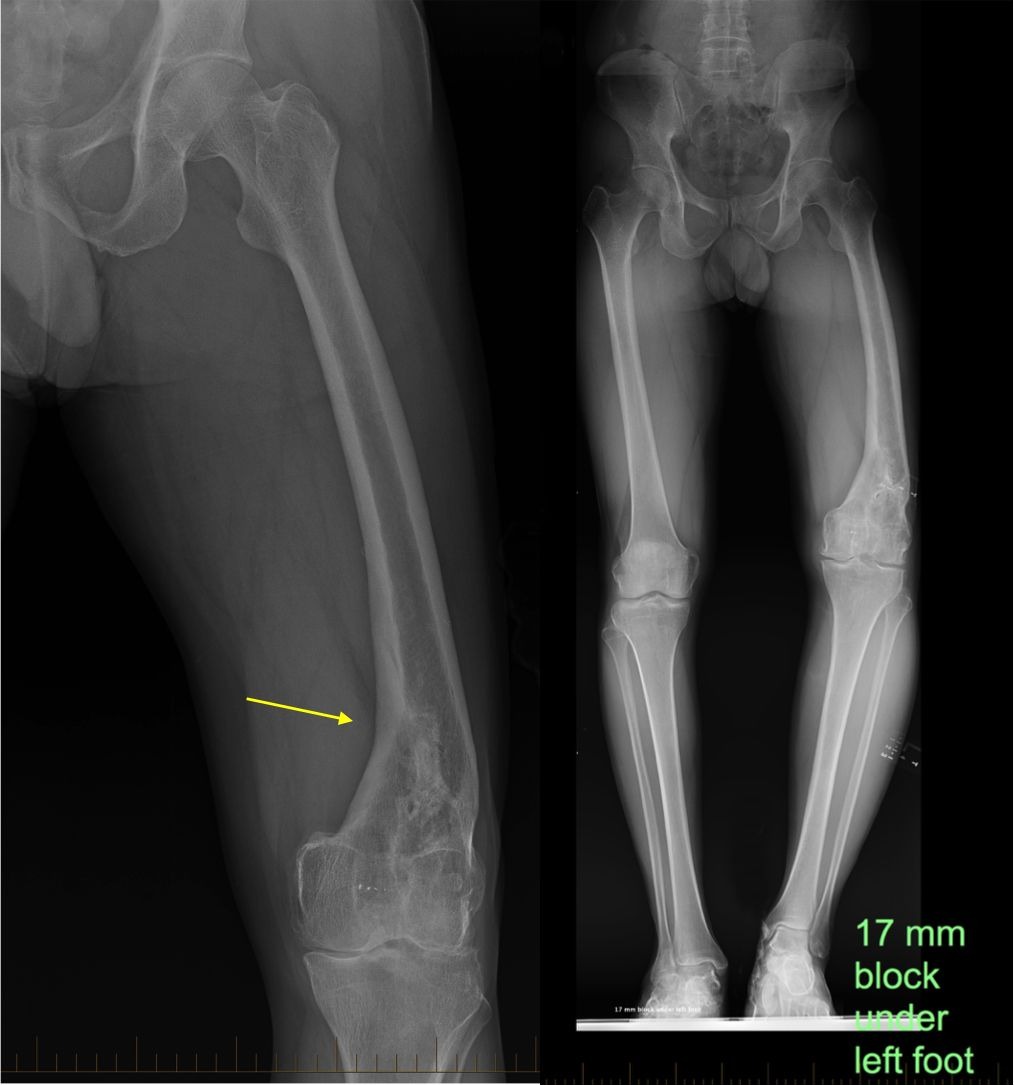

Improper healing of a fractured bone can lead to deformity, pain, and reduced function. Mal-Union Surgery focuses on correcting bone alignment to restore normal movement and balance. At The Derma Joint Co in Jaipur, this procedure is performed with precision to improve both function and comfort.

Led by Dr. Vijay Pilaniya, mal-union correction involves carefully re-aligning the bone and stabilising it using advanced surgical techniques. This correction helps relieve abnormal stress on joints and muscles, which can otherwise cause long-term discomfort.

Accurate planning and rehabilitation are essential to achieving successful outcomes. Patients often experience improved movement, reduced pain, and better posture after recovery.